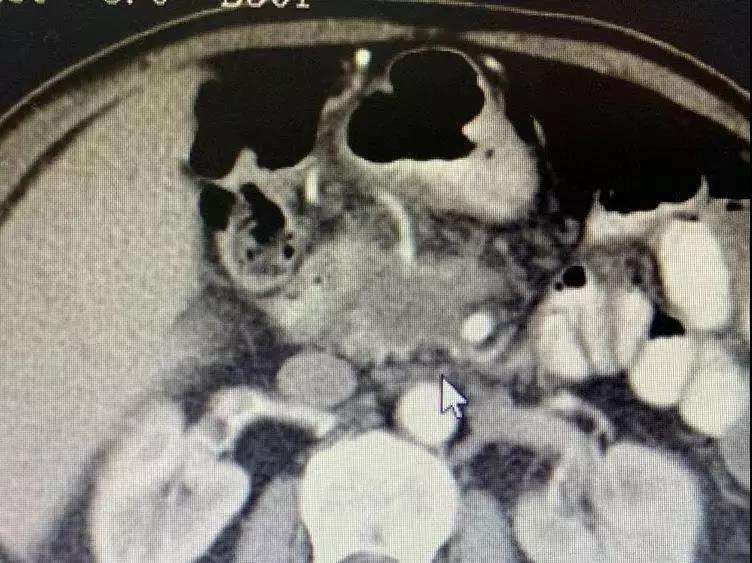

胰腺肿瘤包绕血管,及腹腔淋巴节转移

通过护士了解到,梭和梭的家属都很亲切,打招呼时候总会双手合十放在胸前向你微笑点头,说话也很温和。梭生活在印度教和佛教浓厚的尼泊尔里,连耳垂都与佛有几分相像。梭是今年四月份突发上腹疼痛,五月中旬在当地医院检查发现,“胰腺钩突肿物,有大概3cm大小,肿块邻近肠系膜上静脉”,疑是胰腺癌。在7月25号再次检查发现,病情严重了,出现“侵及肠系膜上静脉及肠系膜上动脉;腔静脉前及主动脉旁多发小淋巴结”;由于医疗条件有限,没有很好的治疗方案。他的医生拉吉夫向他介绍了中国的肿瘤医院。